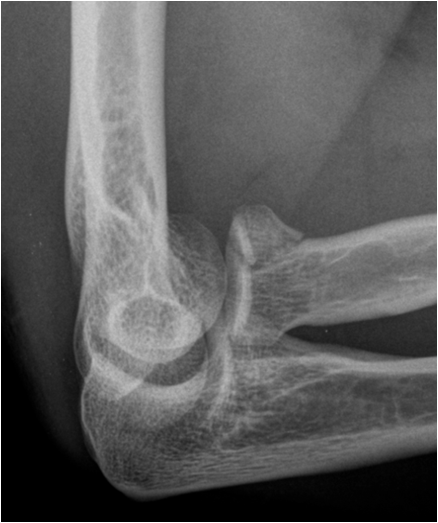

When the range of normal relationships for a particular joint is slightly exceeded, it is called a subluxation. When it is grossly exceeded, and the articulating structures are not in contact any more, it is called a dislocation. Joints most frequently affected by a luxation are shoulder, elbow, ankle, hip, and interphalangeal joints. Luxation will usually cause capsule and ligament disruption with soft tissue swelling and loss of fat planes. Associated avulsion fractures are frequently seen. As in fracture imaging exposure in two perpendicular planes are required to correctly visualize and describe a luxation or dislocated fracture.

Fig. 12. A) Complete dislocation with contraction in the elbow joint. Ulna and radius are both dislocated and dorsally displaced. B.) Anterior and inferior dislocation of the humerus.